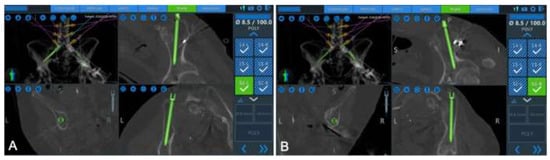

5.3. Novel Robotic Applications

- Dalton, T.; Sykes, D.; Wang, T.Y.; Donnelly, D.; Than, K.D.; Karikari, I.O.; Goodwin, C.R.; Gupta, D.K.; Wiggins, W.F.; Abd-El-Barr, M.M. Robotic-Assisted Trajectory Into Kambin’s Triangle During Percutaneous Transforaminal Lumbar Interbody Fusion-Initial Case Series Investigating Safety and Efficacy. Oper. Neurosurg. 2021, 21, 400–408. [Google Scholar] [CrossRef] [PubMed]

- Park, C.; Crutcher, C.; Mehta, V.A.; Wang, T.Y.; Than, K.D.; Karikari, I.O.; Goodwin, C.R.; Abd-El-Barr, M.M. Robotic-assisted percutaneous iliac screw fixation for destructive lumbosacral metastatic lesions: An early single-institution experience. Acta Neurochir. 2021, 163, 2983–2990. [Google Scholar] [CrossRef] [PubMed]